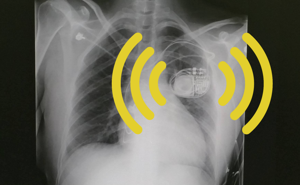

Cloud-connected medical devices save lives, but also raise questions about privacy, security, and oversight. An Object Lesson.